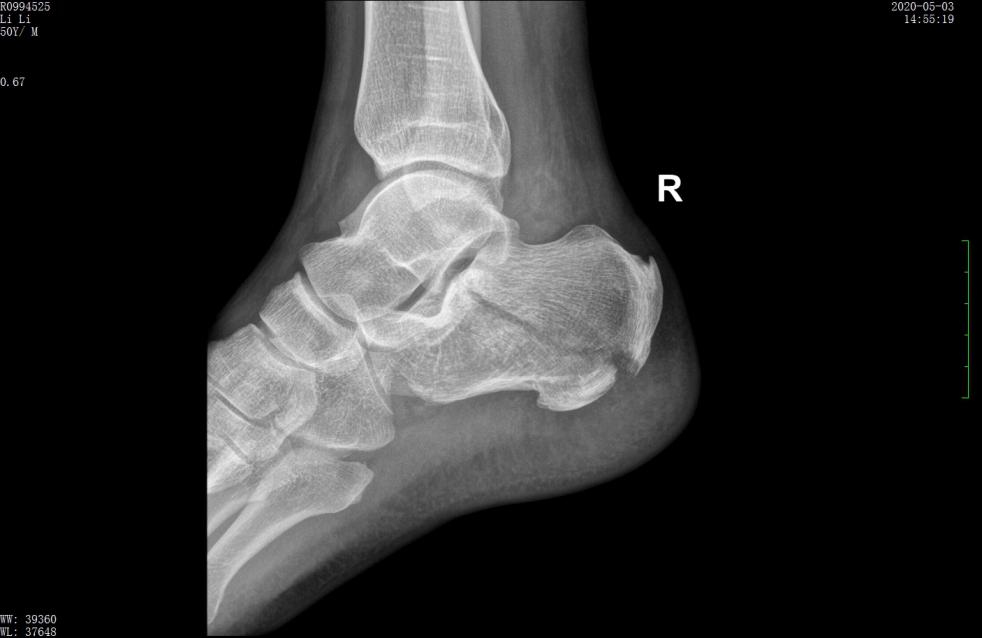

案例2影像

术前X线示骨折分离移位